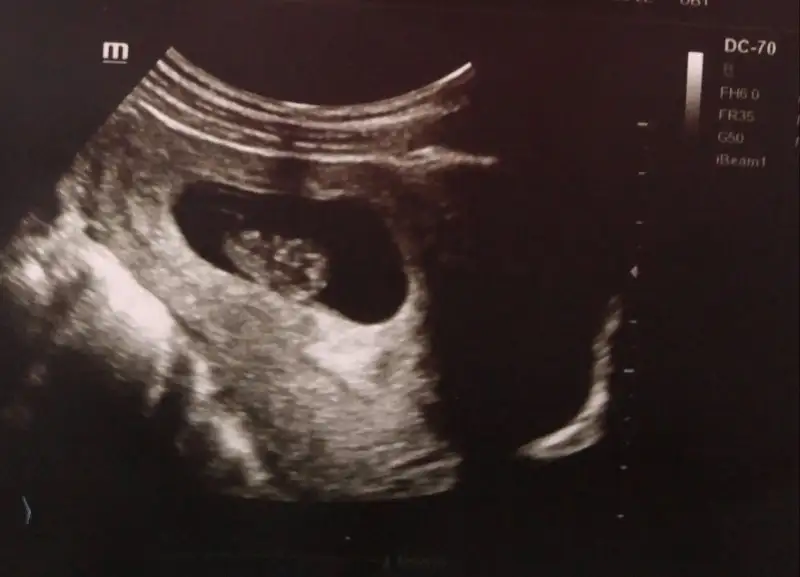

İyi akşamlar kızlar banada bir tahmin yaparmisiniz 13 haftalık abdominal IMG-20180301-WA0024.webp

Cok belli degil ama bugun cekildi :)

• 15208529020661309155539.webp

15208529020661309155539.webp

6,3 KB · Görüntüleme: 139